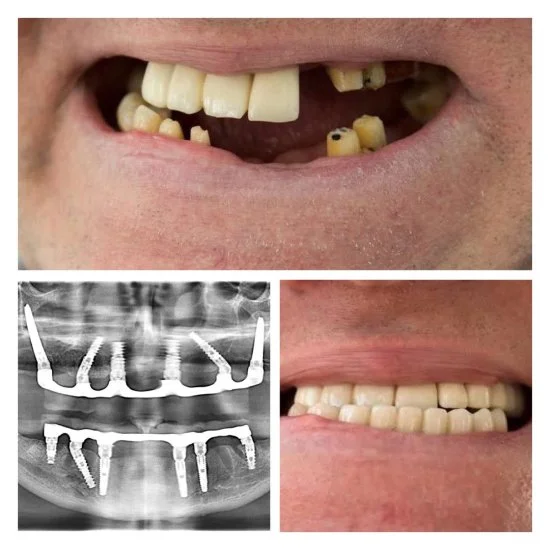

Andrey to doświadczony chirurg stomatolog z ponad 24-letnim stażem. Zajmuje się usuwaniem zębów i implantacją także w trudnych przypadkach — nawet wtedy, gdy inni lekarze nie podejmują się leczenia. Dzięki wiedzy i praktyce potrafi przeprowadzić skomplikowane zabiegi tak, żeby efekt był pewny i przewidywalny.